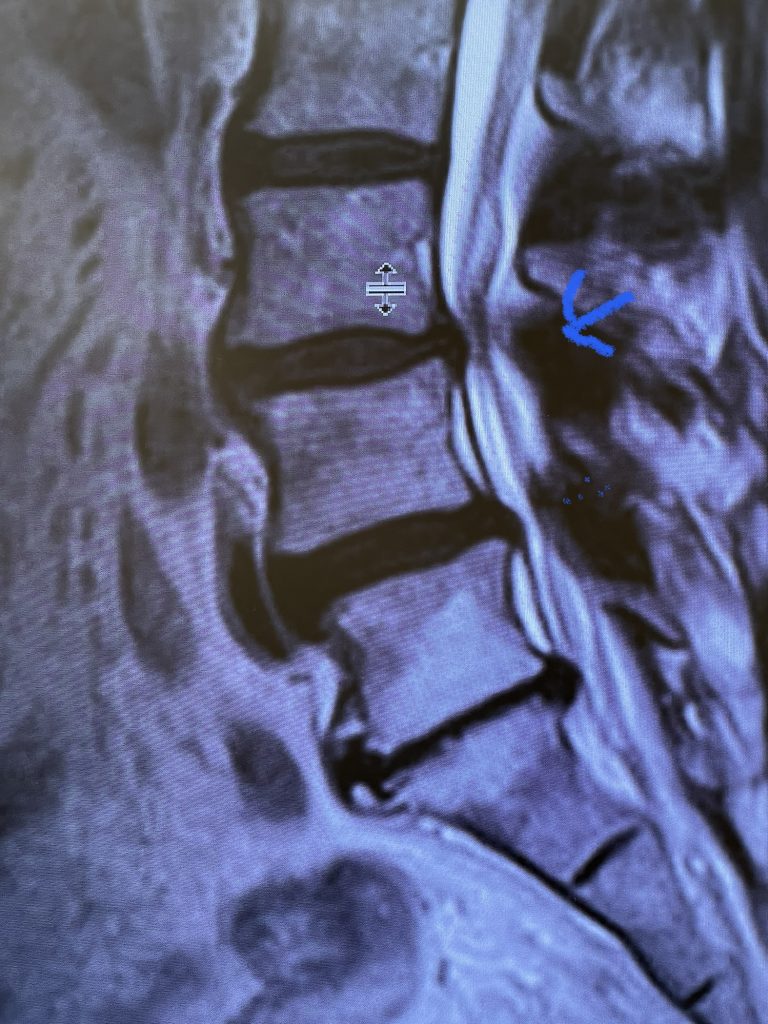

Fig 1: Sagittal and axial T2-weighted MRI images demonstrating a large superiority-oriented synovial cyst (red arrow) at L4-5. The cyst is below the exiting L4 nerve root and hence compresses the descending L5 root. Note the additional thickened ligamentum flavum and slight spondylolistheses at L3-4 and L4-5 (blue arrow).

The patient also had a slight spondylolisthesis at L3-4 and L4-5. The patient failed all means of conservative management including medications, physical therapy, and epidural injections. The patient elected to proceed with a decompressive laminectomy and in-situ fusion. During the procedure we encountered a thick-walled cyst that melded with the dura. We first found the descending left L4 nerve root and separated the cyst and proceeded to in essence bite away the cyst with an instrument. We decompressed the L4 nerve root as it entered its foramina by removing the majority of the cyst wall. There was thick gray gelatinous material within the cyst. Part of the cyst wall seemed to be continuous with the dura and left it alone as it caused no pressure on the root. After our decompression we decided to perform an in-situ fusion as we had relative preservation of the joint complexes. Post operatively, she had an uneventful course with significant relief of her leg pain.